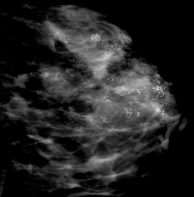

乳腺钼靶其实就是一种专门针对乳腺的X线检查技术,但跟常规的X线比起来,它产生的X线是一种波长相对较长的软射线。钼靶能显示乳腺各层组织,可以发现乳腺各种良、恶性肿瘤以及乳腺其他疾病,可观察到小于0.1mm的微小钙化点及钙化簇,是早期发现和诊断乳腺癌最有效和可靠的检查方法之一,尤其对于临床不可能触及,或超声未能看到的微小钙化灶的早期乳腺癌具有特异性的诊断意义。